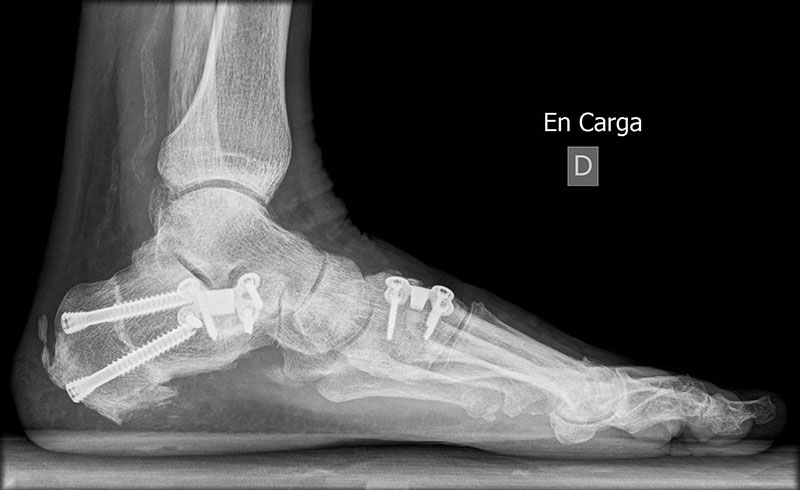

En las deformidades flexibles de retro y mediopie (pie plano, pie cavo) así como en algunos casos de artrosis de tobillo (artrosis asimétrica) abogamos por la preservación articular realizando osteotomías correctoras sin afectar a la movilidad articular.

El tipo de osteotomías, así como los gestos quirúrgicos complementarios será personalizado según la deformidad que presente el paciente.

Después